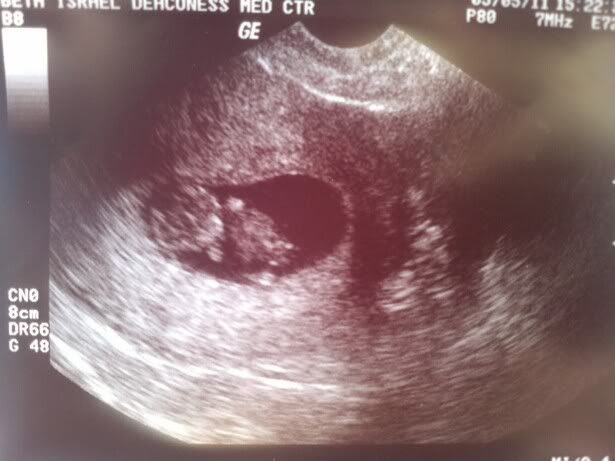

AW: More baby stuff, sorry

I can't help it - I have to share! It's an active little thing and it looked like it was doing a dance when we saw it for the first time yesterday